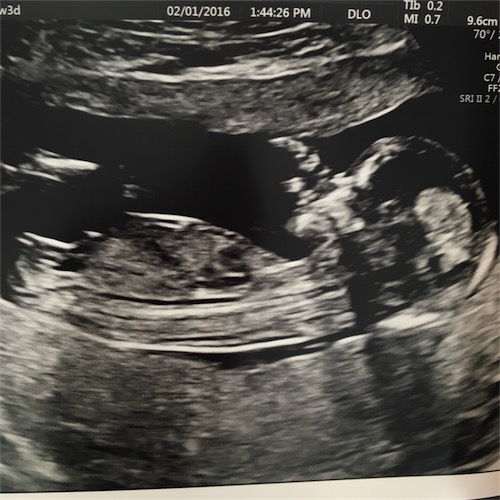

I had my NT scan today at 13 weeks and 3 days, although baby was measuring 13 weeks and 6 days. The tech was familiar with nub theory and made a very confident prediction, which agreed with what both my husband and I had thought as well but I wanted to get other opinions. Thanks in advance.

Attachment 29660